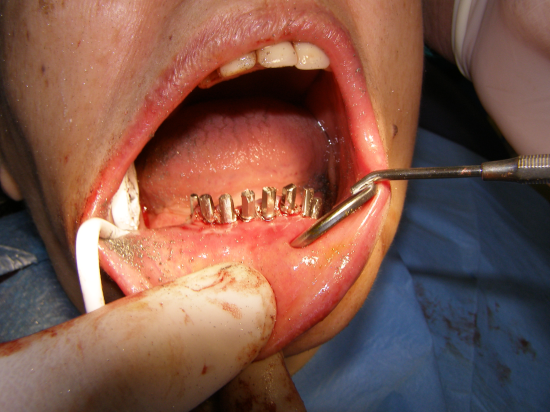

Caso Paziente 3

Donna con grave deficit osseo.Nella parte inferiore è cosi marcato che la paziente ogni qual volta esercitava pressione sulla protesi accusava dolore e parestesia(addormentamento) del viso.Cio'accadeva per la esposizione di un tratto del canale mentoniero(vedi tac) causato dal marcatissimo riassorbimento osseo dovuto anche alla protesi mobile.La paziente è stata trattata in anestesia locale in due sedute per la fase chirurgico-protesica(resina estetica) e successivamente(3 mesi dopo) finalizzata con protesi fisse in metallo-ceramica,